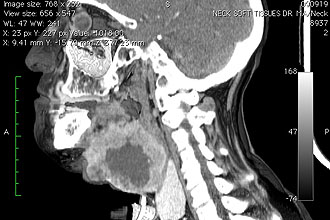

- компьютерную и магнитно-резонансную томографию;